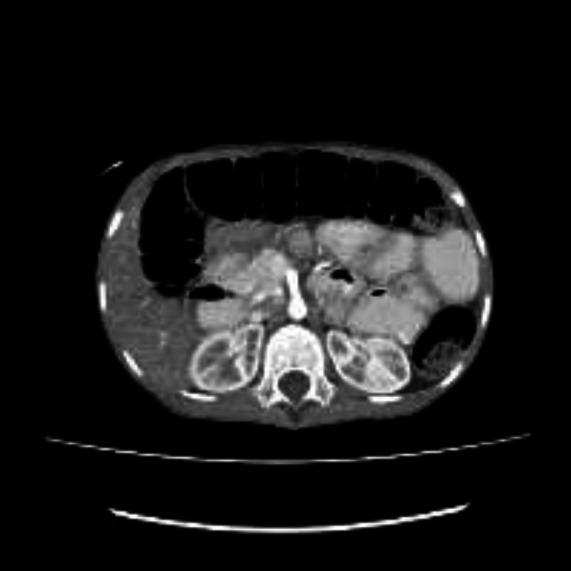

We report this unusual presentation of small intestine volvulus in an 11-year old Nigerian boy who first presented only with anasarca. While being investigated for the cause of the anasarca, he developed features of acute abdomen thought to be spontaneous bacteria peritonitis initially. He had surgery where the diagnosis of small intestine volvulus was made.

我们报告一名11岁尼日利亚男孩小肠扭转的这一不寻常表现,他最初仅表现为全身性水肿。在对全身性水肿的病因进行检查时,他出现了急腹症症状,最初被认为是自发性细菌性腹膜炎。他接受了手术,术中诊断为小肠扭转。